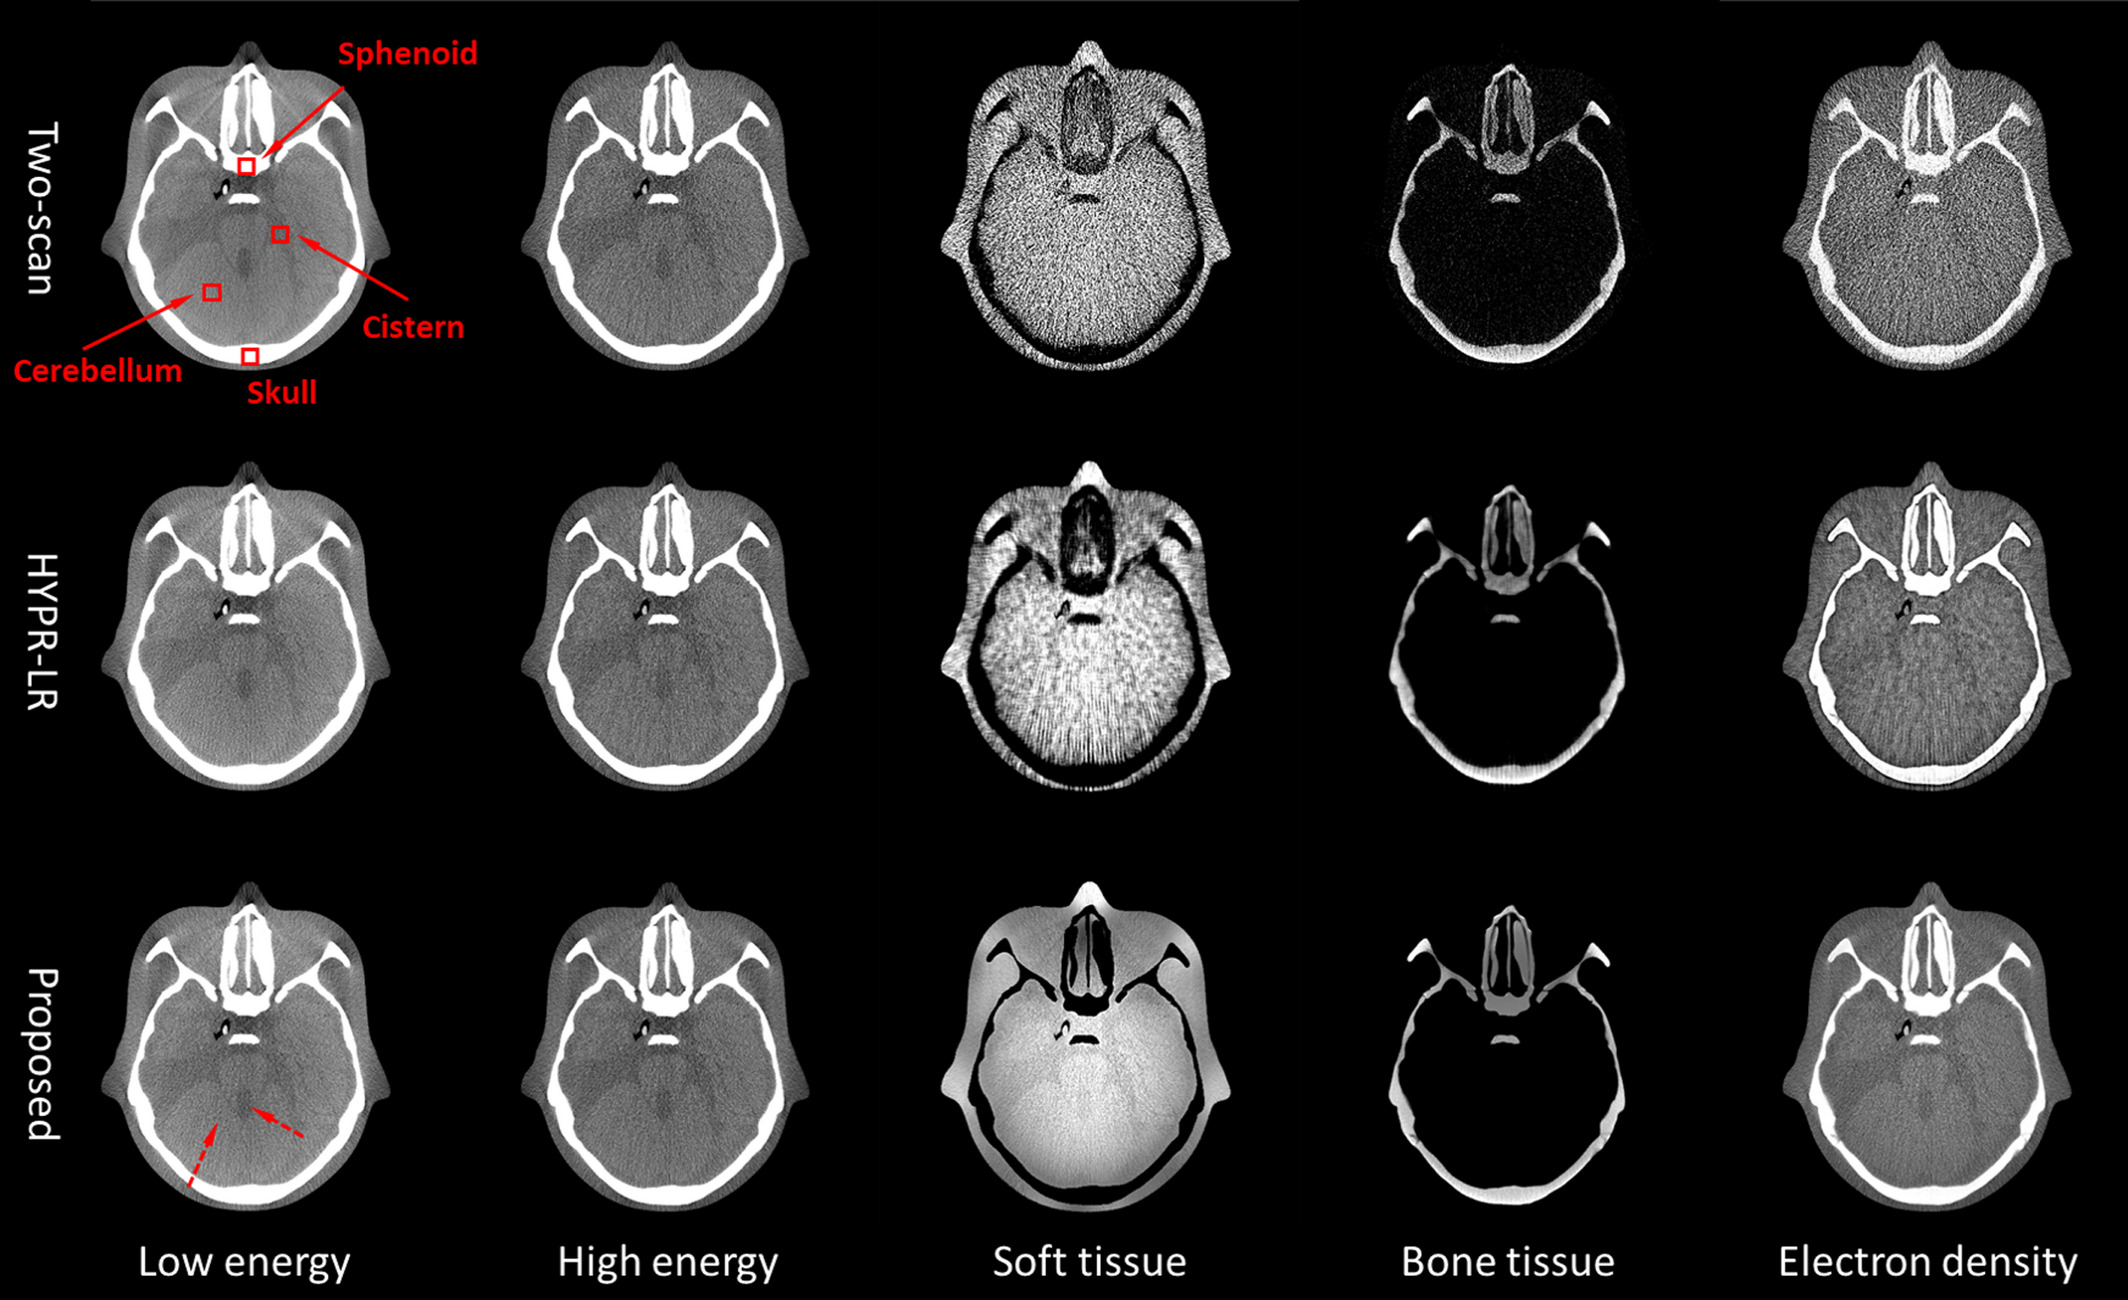

Fast and effective single-scan dual-energy cone-beam CT reconstruction and decomposition denoising based on dual-energy vectorization

Medical Physics | 2021

Flat-panel detector (FPD) based dual-energy cone-beam computed tomography (DE-CBCT) is a promising imaging technique for dedicated clinical applications. In this paper, we proposed a fully analytical method for fast and effective single-scan DE-CBCT image reconstruction and decomposition. A rotatable Mo filter was inserted between an x-ray source and imaged object to alternately produce low and high-energy x-ray spectra. First, filtered-backprojection (FBP) method was applied on down-sampled projections to reconstruct low and high-energy images. Then, the two images were converted into a vectorized form represented with an amplitude and an argument image. Using amplitude image as a guide, a joint bilateral filter was applied to denoise the argument image. Then, high-quality dual-energy images were recovered from the amplitude image and the denoised argument image. Finally, the recovered dual-energy images were further used for low-noise material decomposition and electron density synthesis. Imaging was conducted on a Catphan®600 phantom and an anthropomorphic head phantom. The proposed method was evaluated via comparison with the traditional two-scan method and a commonly used filtering method (HYPR-LR). On the Catphan®600 phantom, the proposed method successfully reduced streaking artifacts and preserved spatial resolution and noise-power-spectrum (NPS) pattern. In the electron density image, the proposed method increased contrast-to-noise ratio (CNR) by more than 2.5 times and achieved <1.2% error for electron density values. On the anthropomorphic head phantom, the proposed method greatly improved the soft-tissue contrast and the fine detail differentiation ability. In the selected ROIs on different human tissues, the differences between the CT number obtained by the proposed method and that by the two-scan method were less than 4 HU. In the material images, the proposed method suppressed noise by over 75.5% compared with two-scan results, and by over 40.4% compared with HYPR-LR results. Implementation of the whole algorithm took 44.5 s for volumetric imaging, including projection preprocessing, FBP reconstruction, joint bilateral filtering, and material decomposition. Using down-sampled projections in single-scan DE-CBCT, the proposed method could effectively and efficiently produce high-quality DE-CBCT images and low-noise material decomposition images. This method demonstrated superior performance on spatial resolution enhancement, NPS preservation, noise reduction, and electron density accuracy, indicating better prospect in material differentiation and dose calculation.